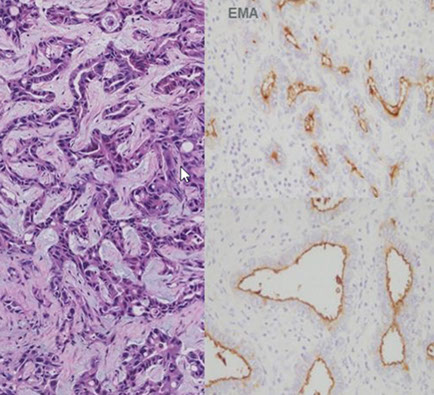

If livers c advanced fibrosis are started on immunosuppressive tx, may form regenerative nodules that mimic tumors or imaging studies and gross exam

Micro: Very active interface and lobular hepatitis

- Abundant plasma cells in clusters, eosinophils

- Regenerative periportal liver cell rosettes

- Severe bridging necrosis, cirrhosis